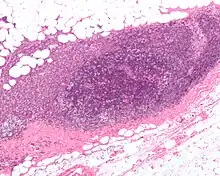

MRI showing breast cancer High-grade invasive ductal carcinoma, with minimal tubule formation, marked pleomorphism, and prominent mitoses, 40x field

High-grade invasive ductal carcinoma, with minimal tubule formation, marked pleomorphism, and prominent mitoses, 40x field Micrograph showing a lymph node invaded by ductal breast carcinoma, with an extension of the tumor beyond the lymph node

Micrograph showing a lymph node invaded by ductal breast carcinoma, with an extension of the tumor beyond the lymph node_expression_in_normal_breast_and_breast_carcinoma_tissue.jpg.webp) Neuropilin-2 expression in normal breast and breast carcinoma tissue